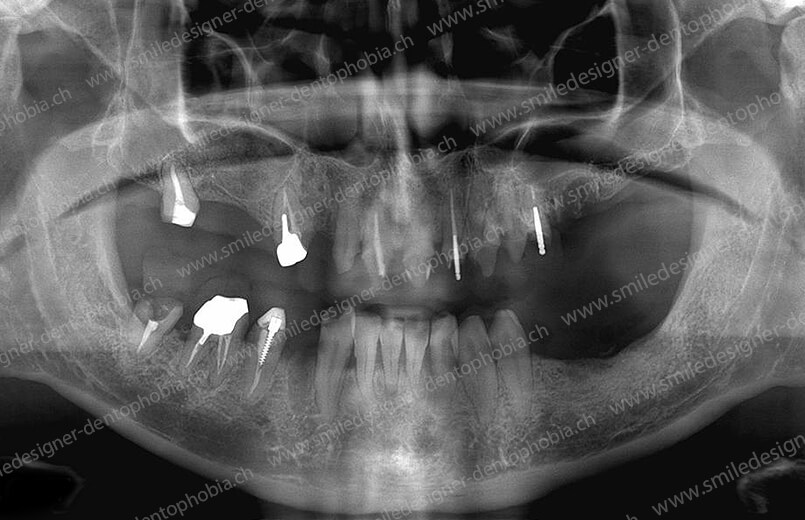

Cas clinique « GOLD STANDARD MCI » bi-maxillaire : Bridge implanto-porté sans extension postérieure (ALL ON 8/8). Version définitive des bridges avec un cosmétique en céramique.

BRIDGE RÉSILIENT PROTOTYPE DE PREMIÈRE INTENTION DE MISE EN CHARGE IMMÉDIATE 4 JOURS APRÈS LA POSE DES IMPLANTS POUR UNE RESOCIALISATION IMMÉDIATE DU PATIENT

CAS EN COURS D’OSTÉOINTÉGRATION DES IMPLANTS BI-MAXILLAIRES.